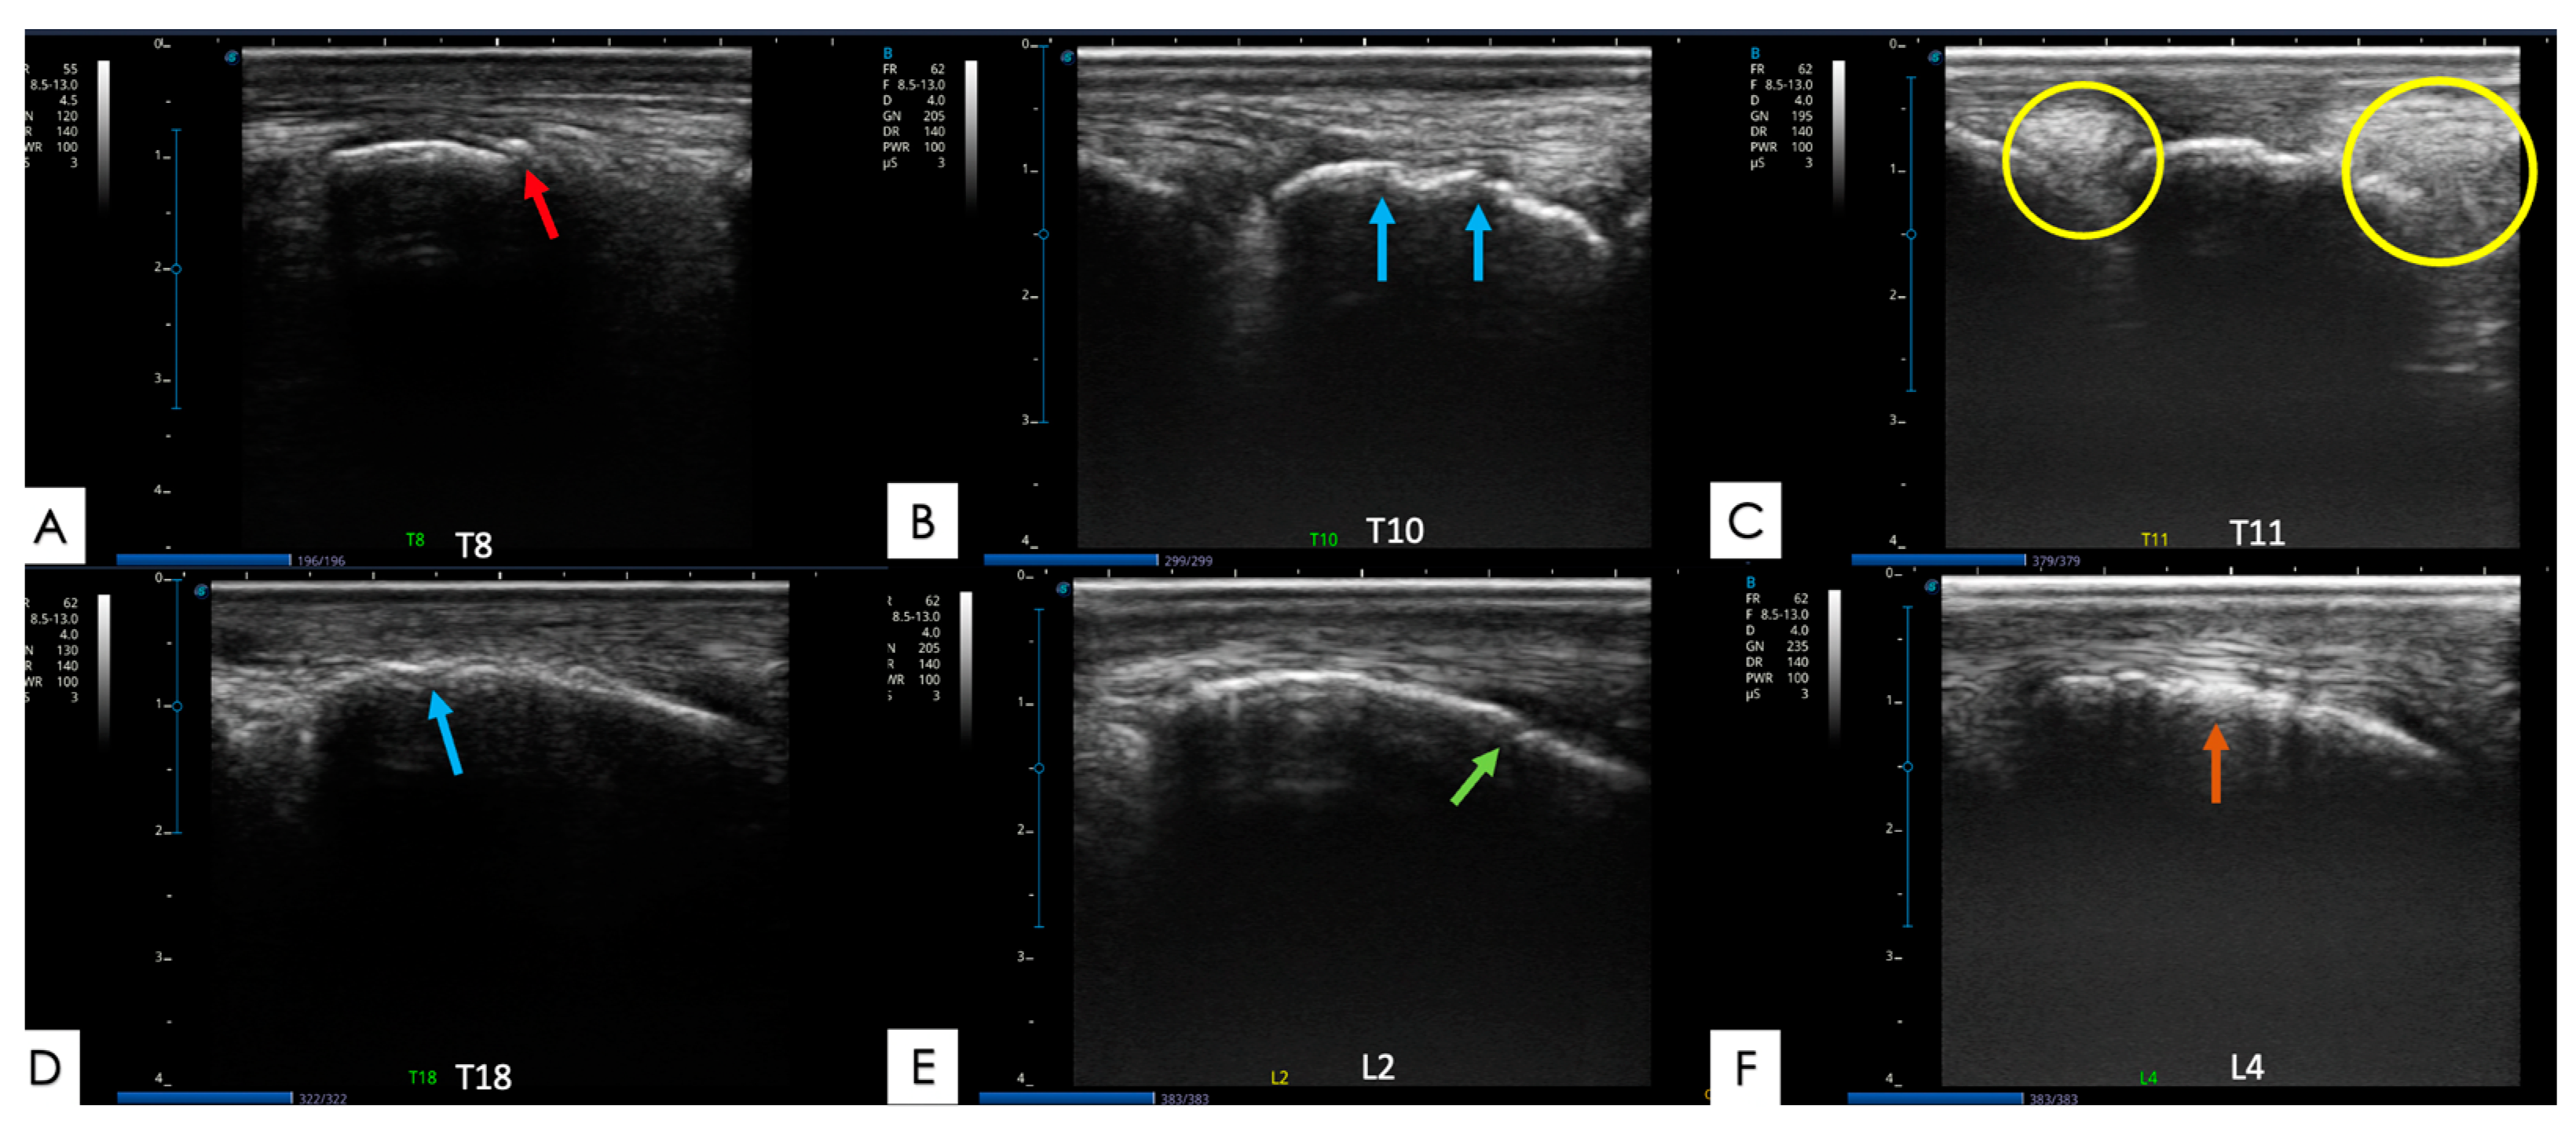

2.5.2. Spinous Processes and Supraspinous Ligament